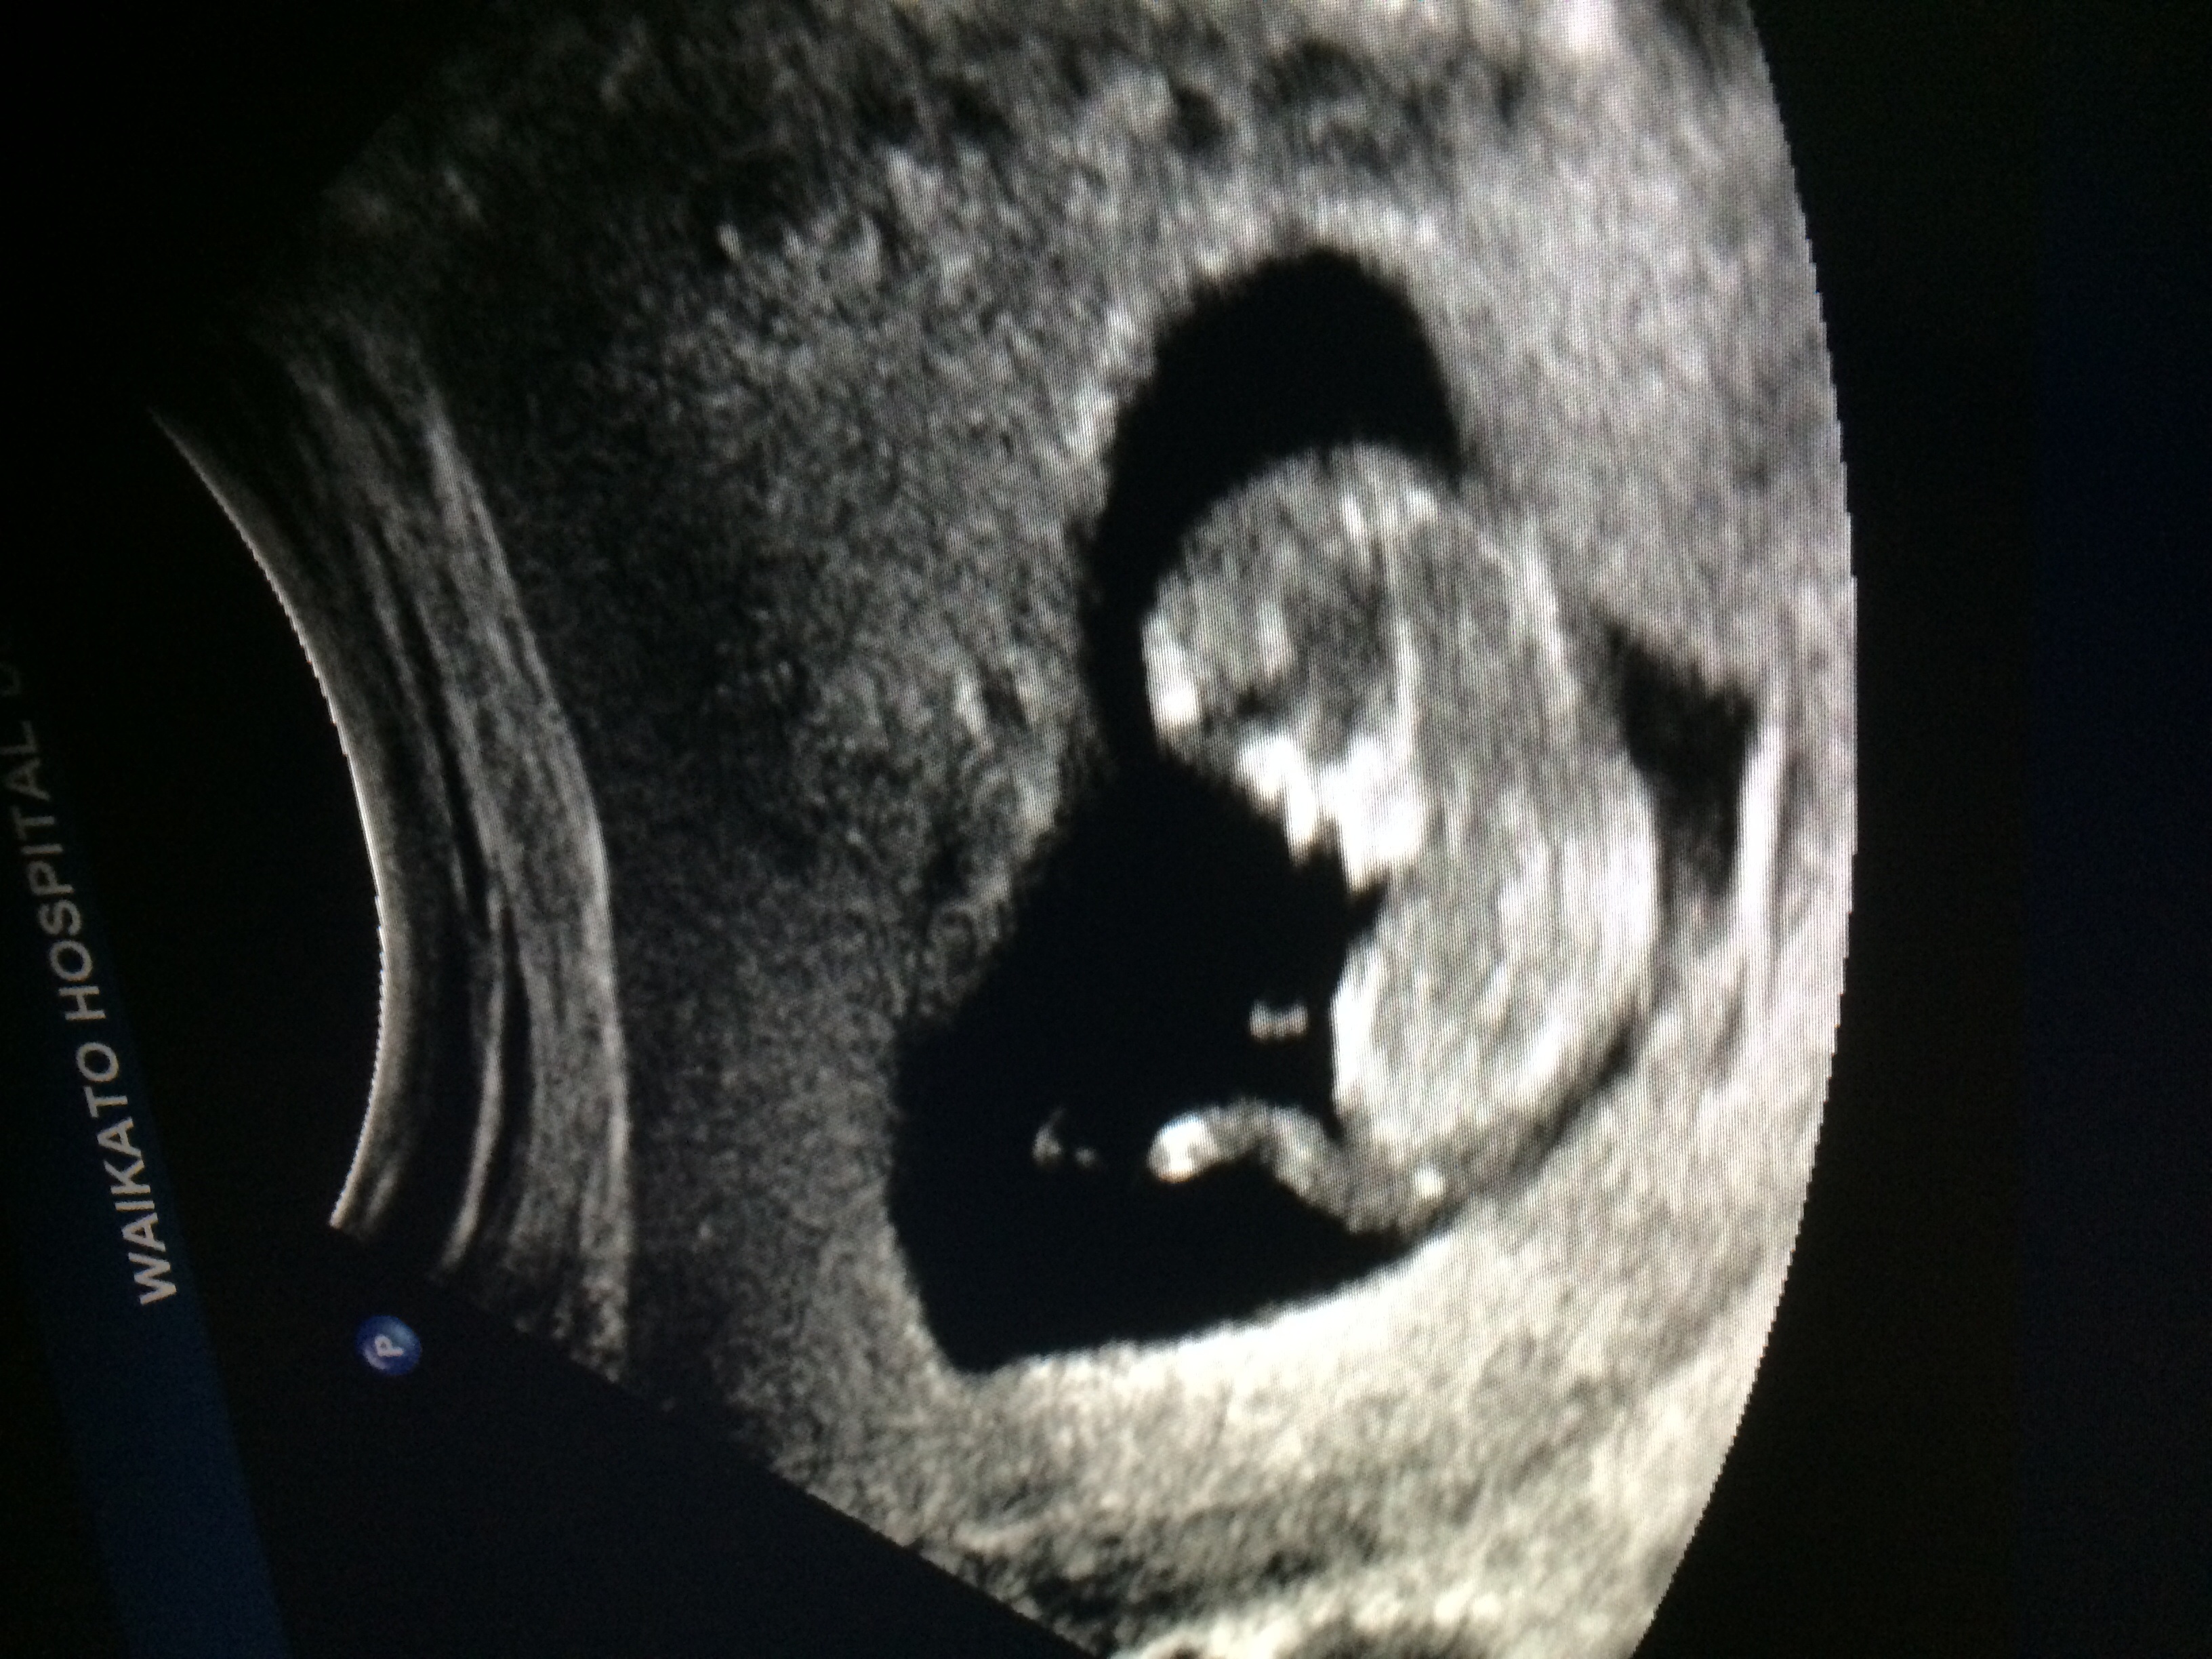

Got a great pic of our baby at 9w6d yesterday! Baby was verrrryy squirmy and was moving around. It was amazing to see baby active! Heart rate was 167 but she said that it was probably high because baby was moving so much! Due date February 24th.